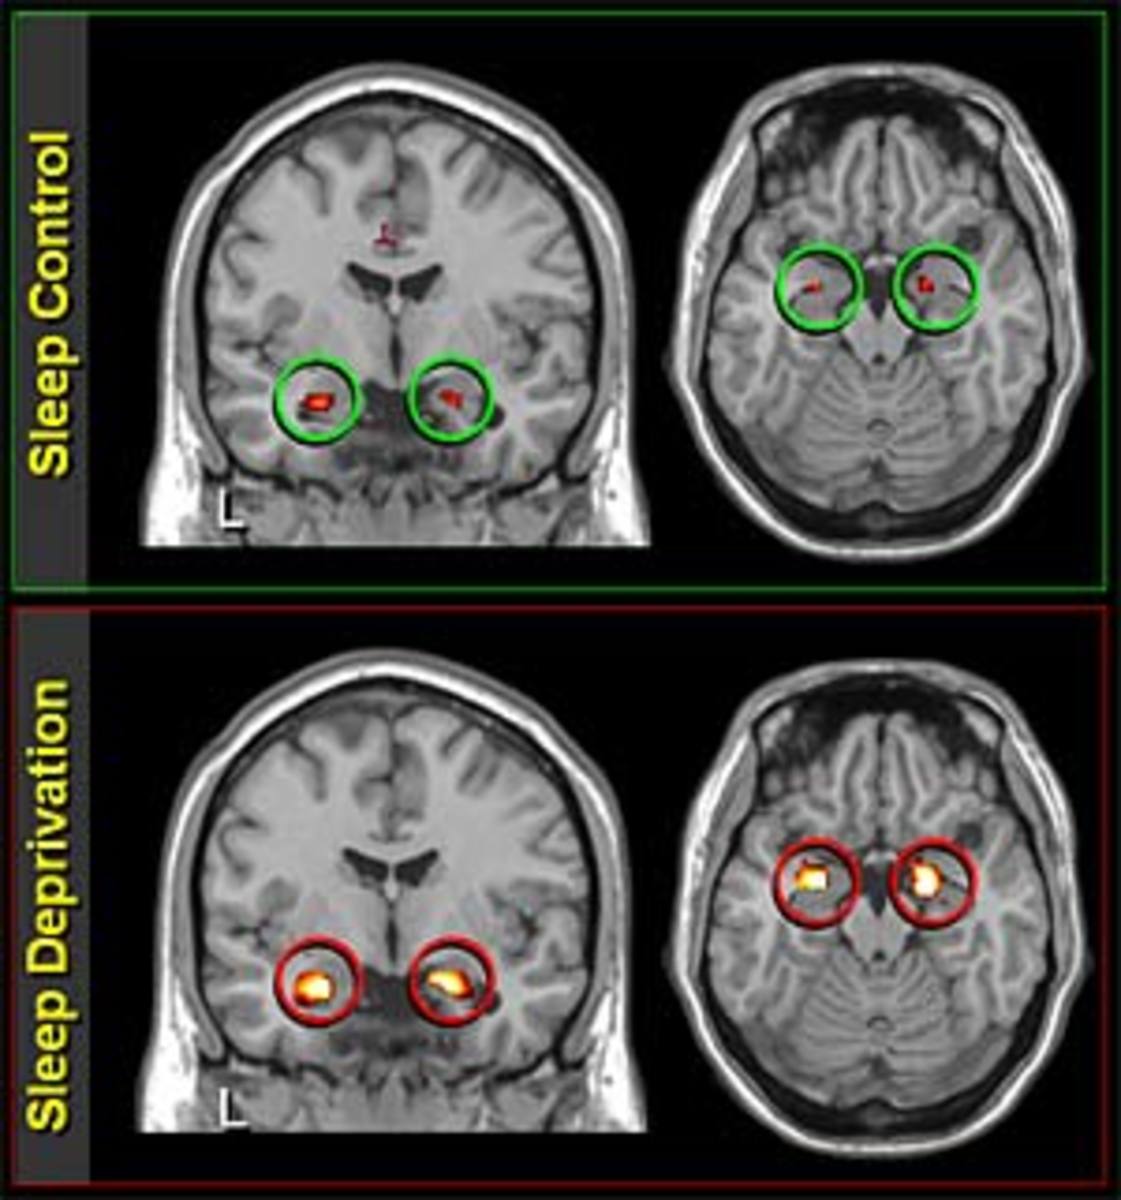

The impact of sleep deprivation on emotional brain reactivity and Sleeping Under The Covers Brain Damage According to g9sleeptight.com (and many other websites), sleeping with the head under the blanket. It can actually trigger a sleep response,” dr. Under a heavy blanket) can cause brain issues and thus. Sleeping with your head under the covers offers protection from external stimulation, dulling any light and muffling sounds, making sleeping easier at night. Additionally, covering your head while. Sleeping Under The Covers Brain Damage.